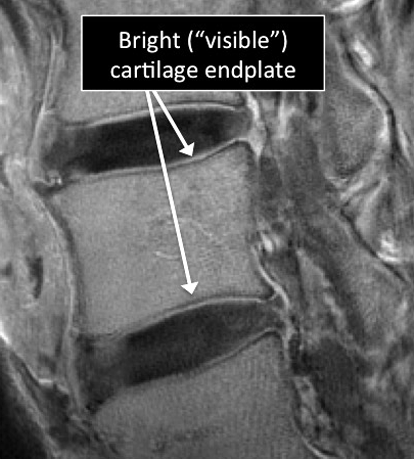

Why Translational MRI of the wrist?

- In the spine, as in many other parts of the body there are certain structures that can’t be seen (they look black or dark) with the standard MRI.

- There are new “software” programs that allow us to see structures with different contrast (bright versus dark).

- Some of these “invisible” or dark structures are unique to the spine (vertebral endplate) and others are found in other parts of the body (e.g. ligaments, cortical bone, nerves).

Spine MRI examinations using the standard MRI techniques (top) and translational MRI techniques (bottom).